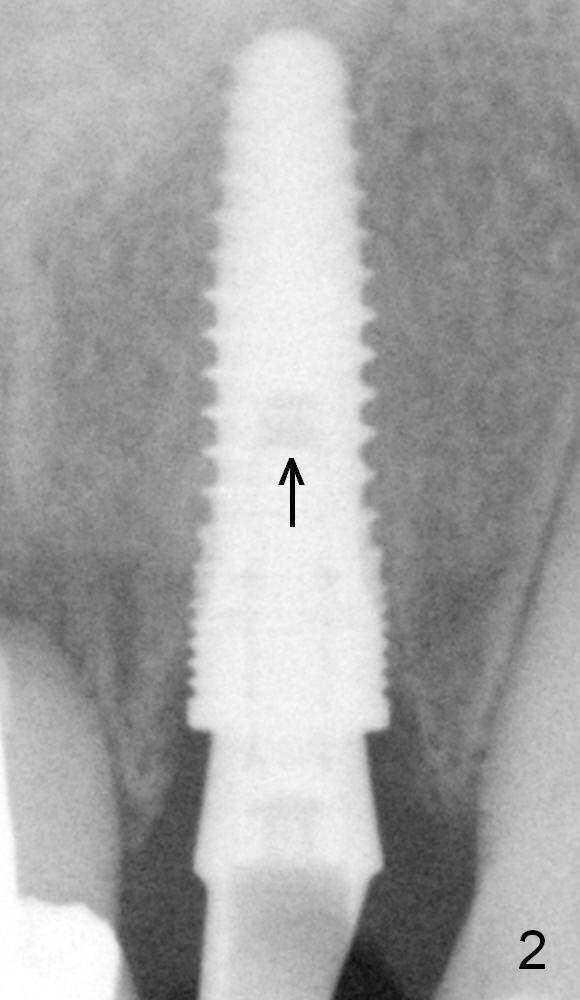

Fig.1,2 show the abutment (A) before and after torquing, respectively.  After the torquing, the abutment turns mesially (Fig.2 white arrow) and apparently ascends slightly (black arrow).  The height of the space inside the implant (I) is shortened after torquing (compare Fig.1,2).  In other word, the abutment was incompletely seated prior to torquing.